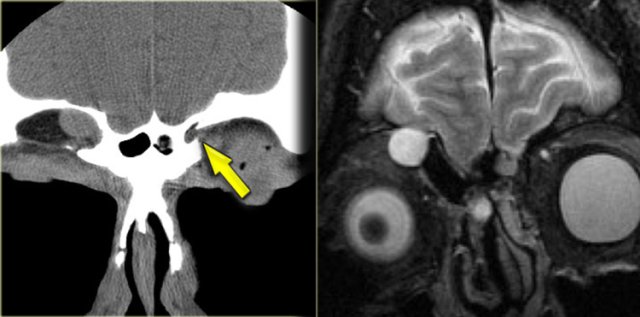

On the left a T2W-image in an immuno-compromised patient with fever.

Initially a MRI was performed to rule out sinusitis.

Notice the low signal intensity of the left sphenoid sinus, which also had a low signal intensity on the T1W-image (not shown).

Continue with the CT.

Pseudo-pneumatized sinus on MR. Beware of fungus! Pseudo-pneumatized sinus on MR. Beware of fungus!

The CT clearly shows the opacified sinus, which is slightly hyperdense.

The signal characteristics on MRI and the attentuation on CT are a result of the high protein content of fungus.

This is a good example of the pitfall of the 'pseudo-pneumatized sinus' .

This is an example of an Actinomyes infection.

So, when invasive fungal infection is suspected, start with a CT, then move on to MRI to rule out spread to the eye, cavernous sinus and intracranial compartment!